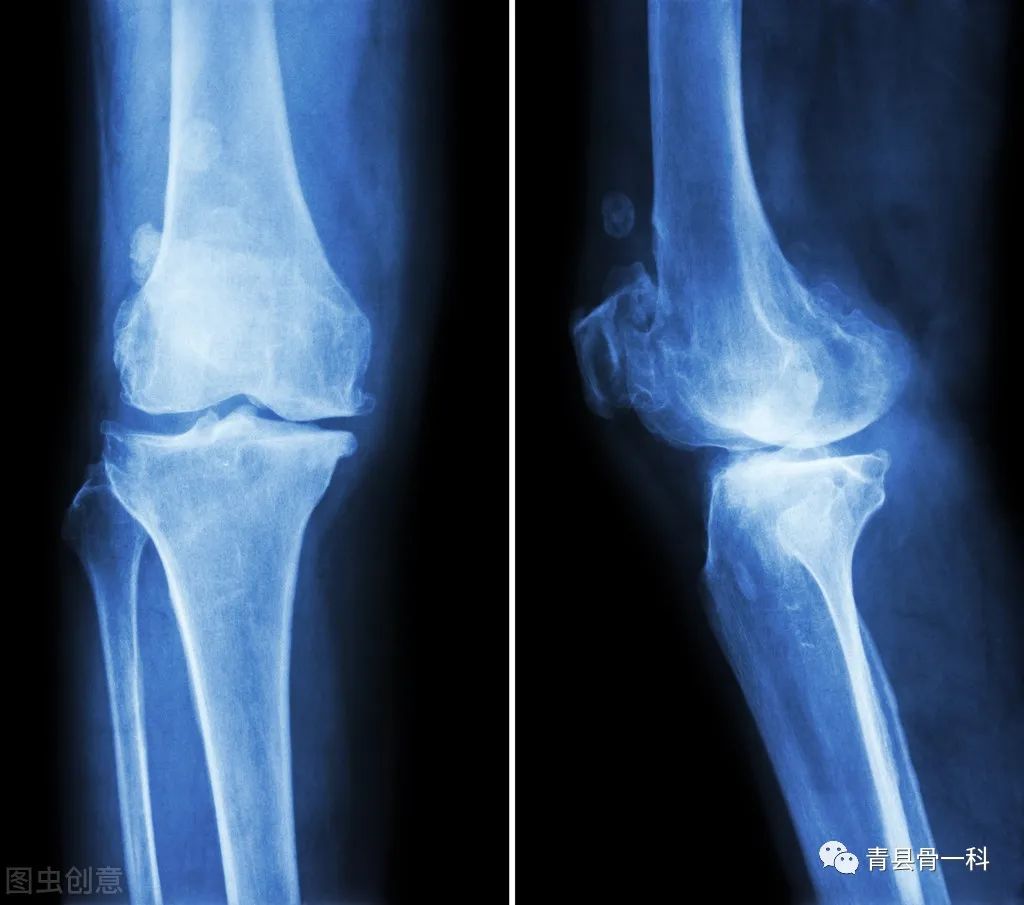

骨质增生是身体骨骼一种自然蜕变的衰老过程,它是属于正常的身体现象,也是身体骨骼衰退的一种自我保护,大部分骨质疏松是通过影像检查发现。在生活中40岁以上的中老年人有20%存在骨质增生,60岁以上的老年人有80%存在。

很多人认为骨刺就像动物骨头一样,如鱼骨刺,会扎在肉里面导致疼痛,但其实骨刺是生长在软骨骨组织当中,它并不会扎在肌肉里面导致疼痛,在患有骨刺后肌肉疼痛大部分是因为骨质增生压迫神经导致,要注意并不是疼痛就需要治疗。